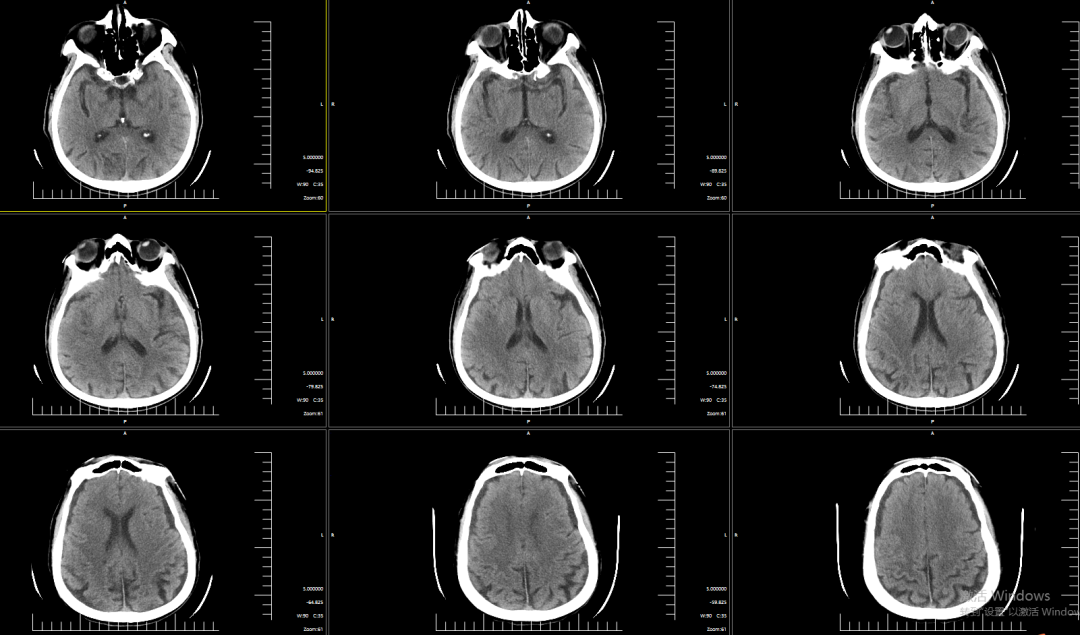

术前影像学检查结果

NCT提示双侧基底节区腔隙性脑梗塞。

DWI提示右侧岛叶、右侧额顶叶明显弥散受限。

CTA提示右侧大脑中动脉M2段下干闭塞。

CTP提示核心梗死体积2.4ml,Mismatch体积160.8ml,低灌注区体积163.2ml,Mismatch比值为68。